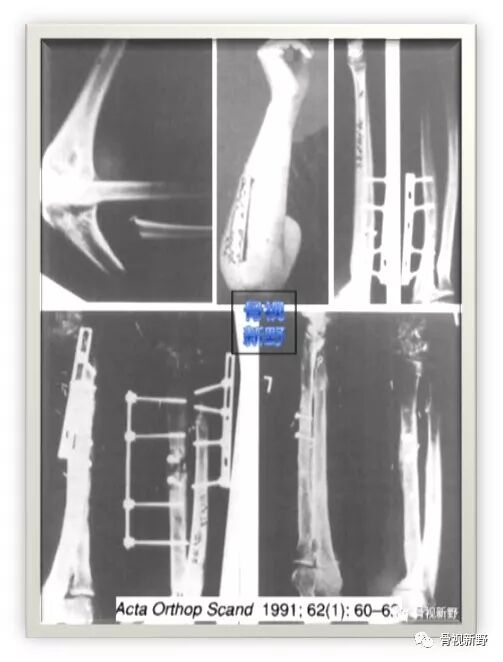

第二次报道:

1991年,Rene K.Marti等人再次报道了将AO钢板作为外固定架用于开放性骨折以及骨感染性的固定病例12例,也取得了较好的疗效。

锁定钢板的外固定应用

Cases